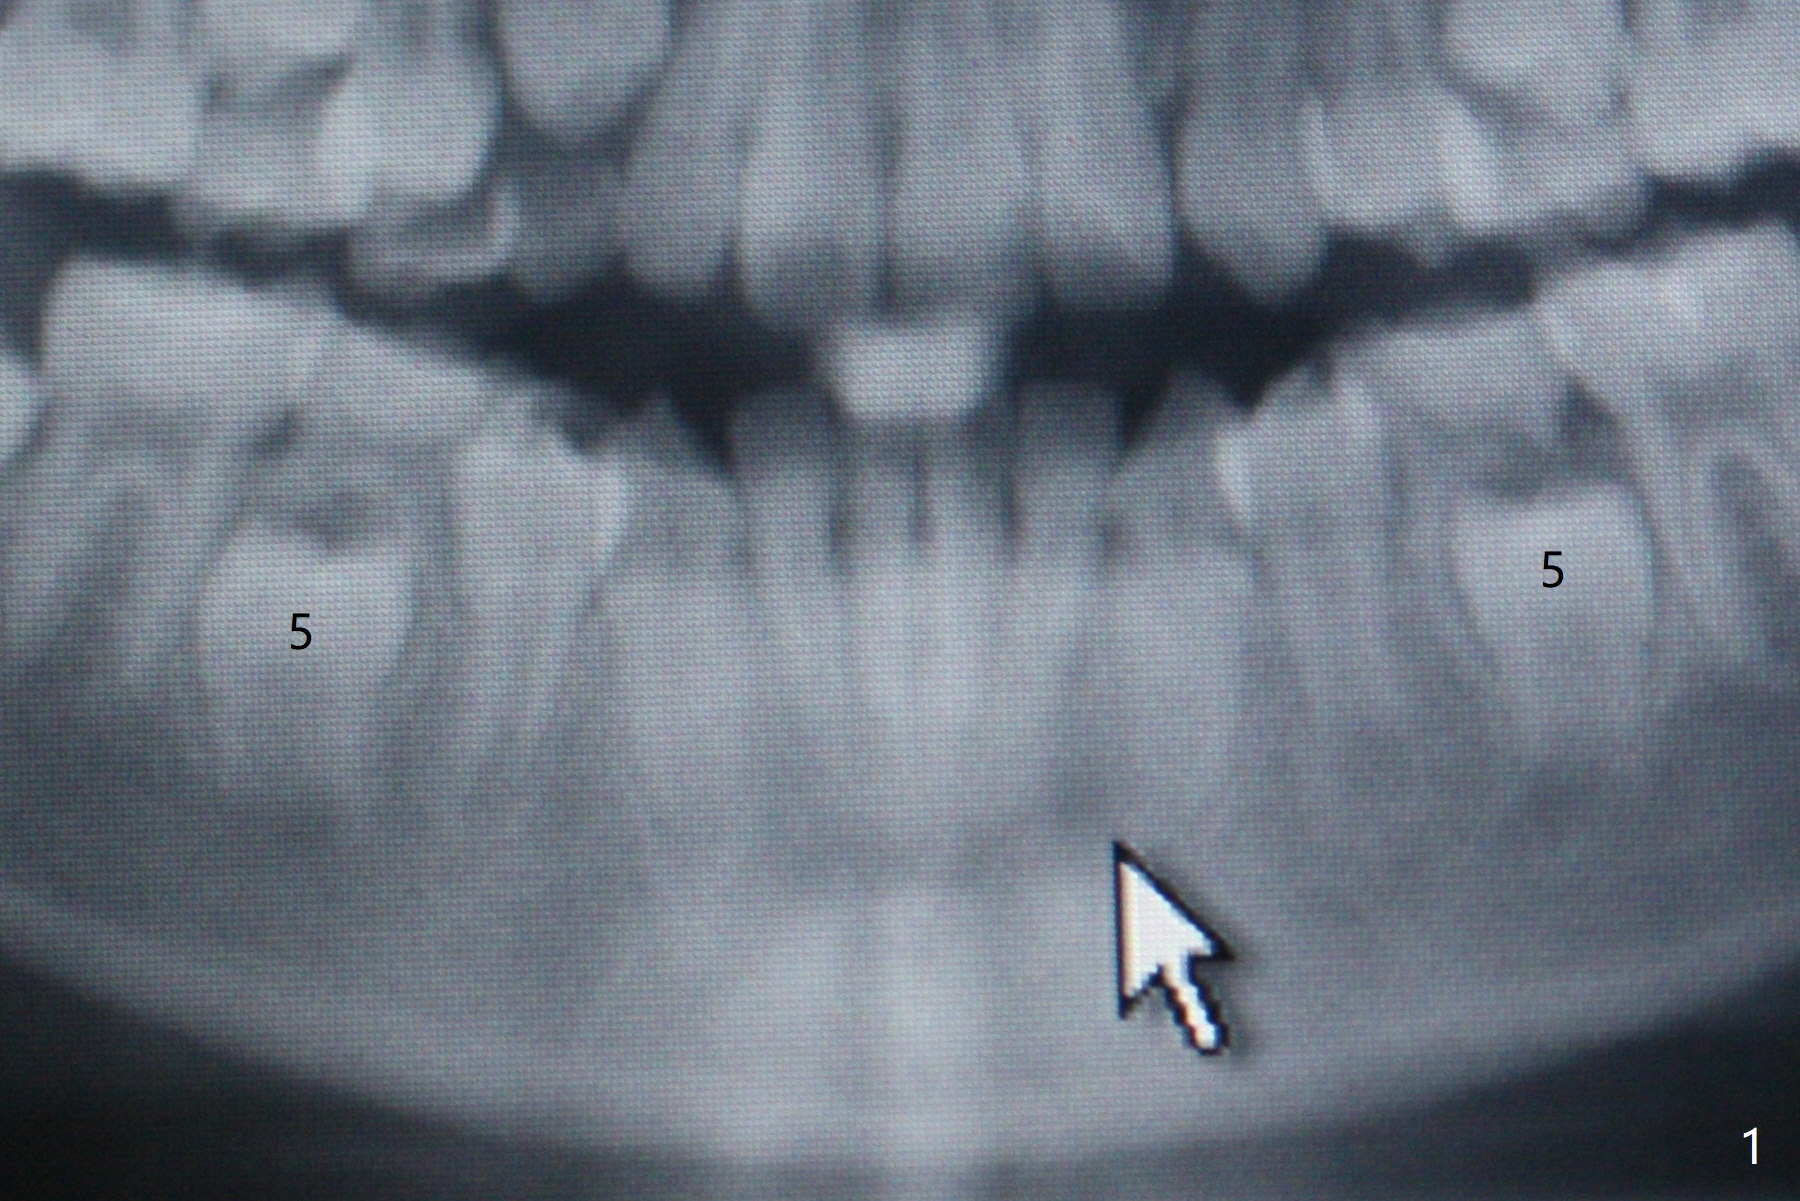

The lower right 2nd bicuspid of a 10-year-old woman seems to rotate before eruption (Fig.1: 5) and remains so when it erupts (Fig.2, at the age of 12).